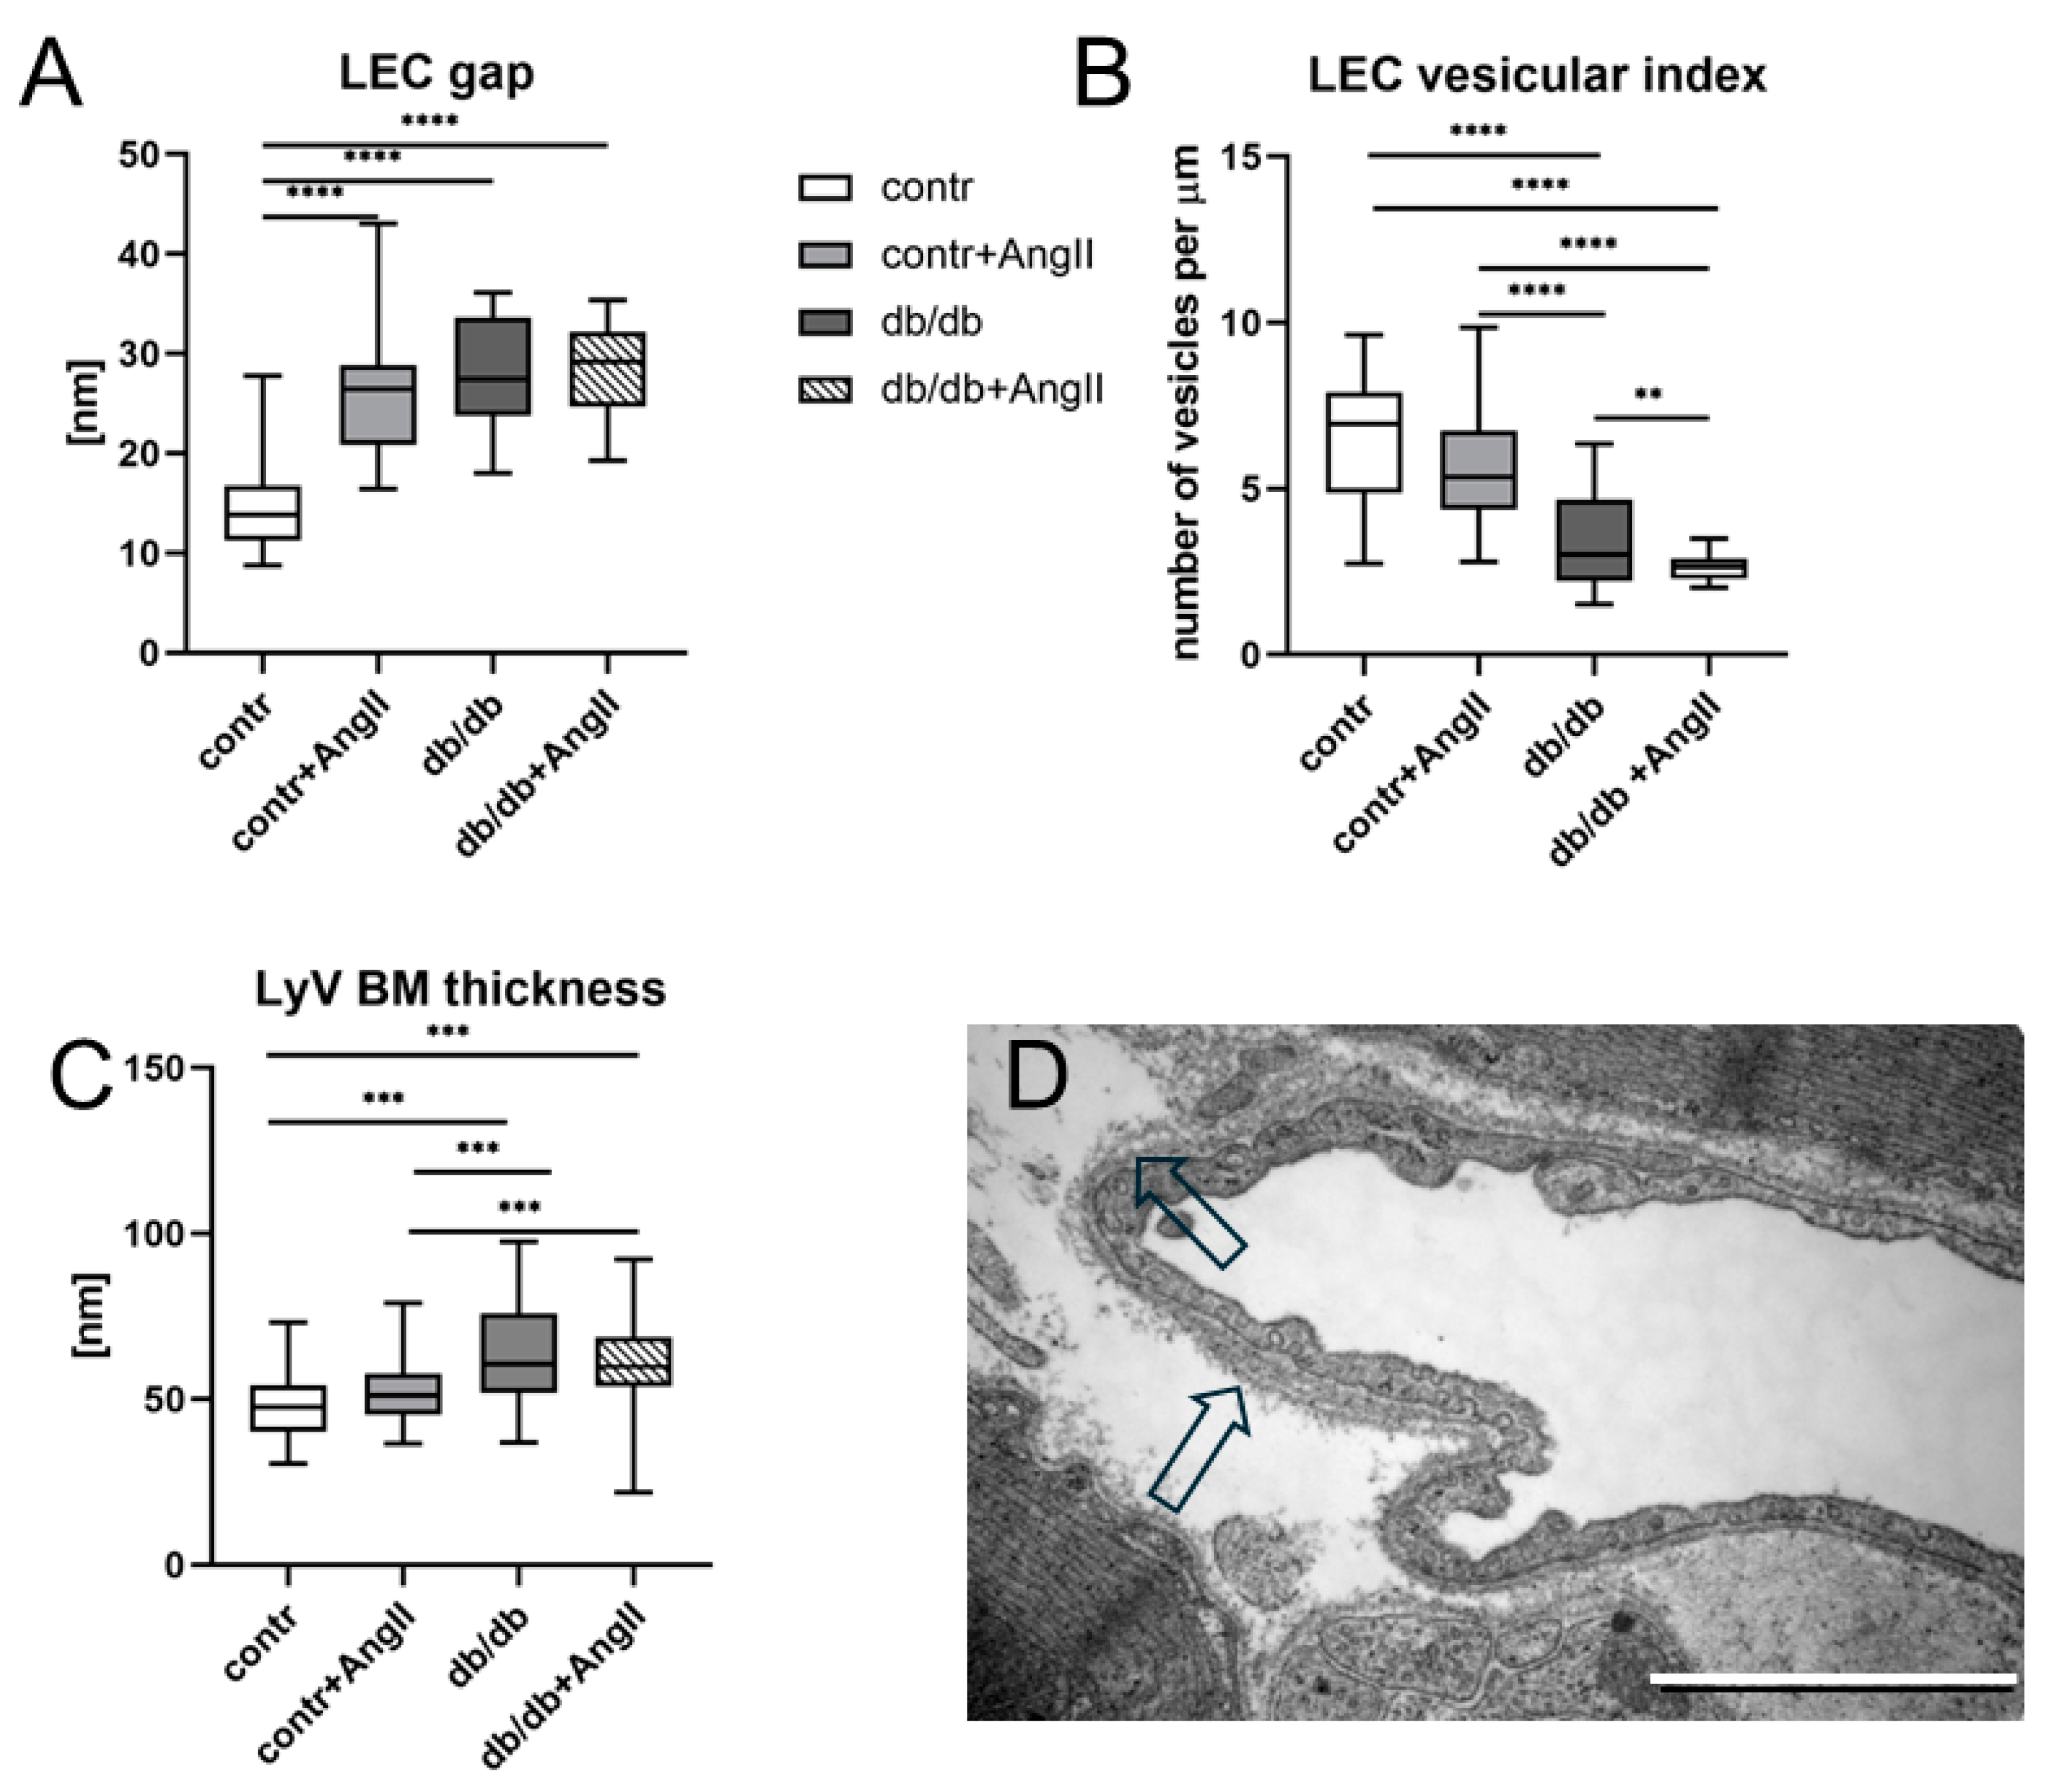

2.7. Ultrastructure and Morphometric Analysis

3.3. Cardiac LyV Density and Structural Remodeling

4.4. LyV Remodeling Is Part of Cardiac Remodeling